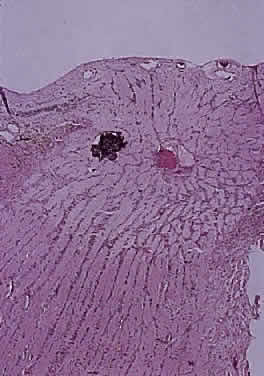

Intraoperatively, hemangioblastoma appears as a reddish, circumscribed tumor that typically is well demarcated from the nerve, although often the central portion is involved. Microscopically, the most striking feature is the abundance of vascular channels, most of which have the appearance of capillaries. Reticulin-staining highlights the vascular network. Between them are stromal cells containing abundant vacuolated cytoplasm, which is due to the presence of lipid. Although bland, the nuclei of the stromal cells are variable in appearance and may exhibit focal marked hyperchromasia (Figs. 46 and 47). Electron microscopy shows that the large stromal cells contain intracytoplasmic particles of lipid and glycogen. Scattered foci of extramedullary hematopoiesis may be present as a consequence of erythropoietin production by the tumor cells. Mast cells also are often readily identifiable. Small cysts are frequent, and the cyst wall consists of gliosis, in which may be found numerous Rosenthal fibers.

Fig. 46. Hemangioblastoma of optic nerve. Multiple capillary vessels are separated by foamy cells (hematoxylin and eosin staining).

Fig. 47. Hemangioblastoma of optic nerve. Foamy cells are a prominent feature between the thin-walled capillary vessels (hematoxylin and eosin staining).